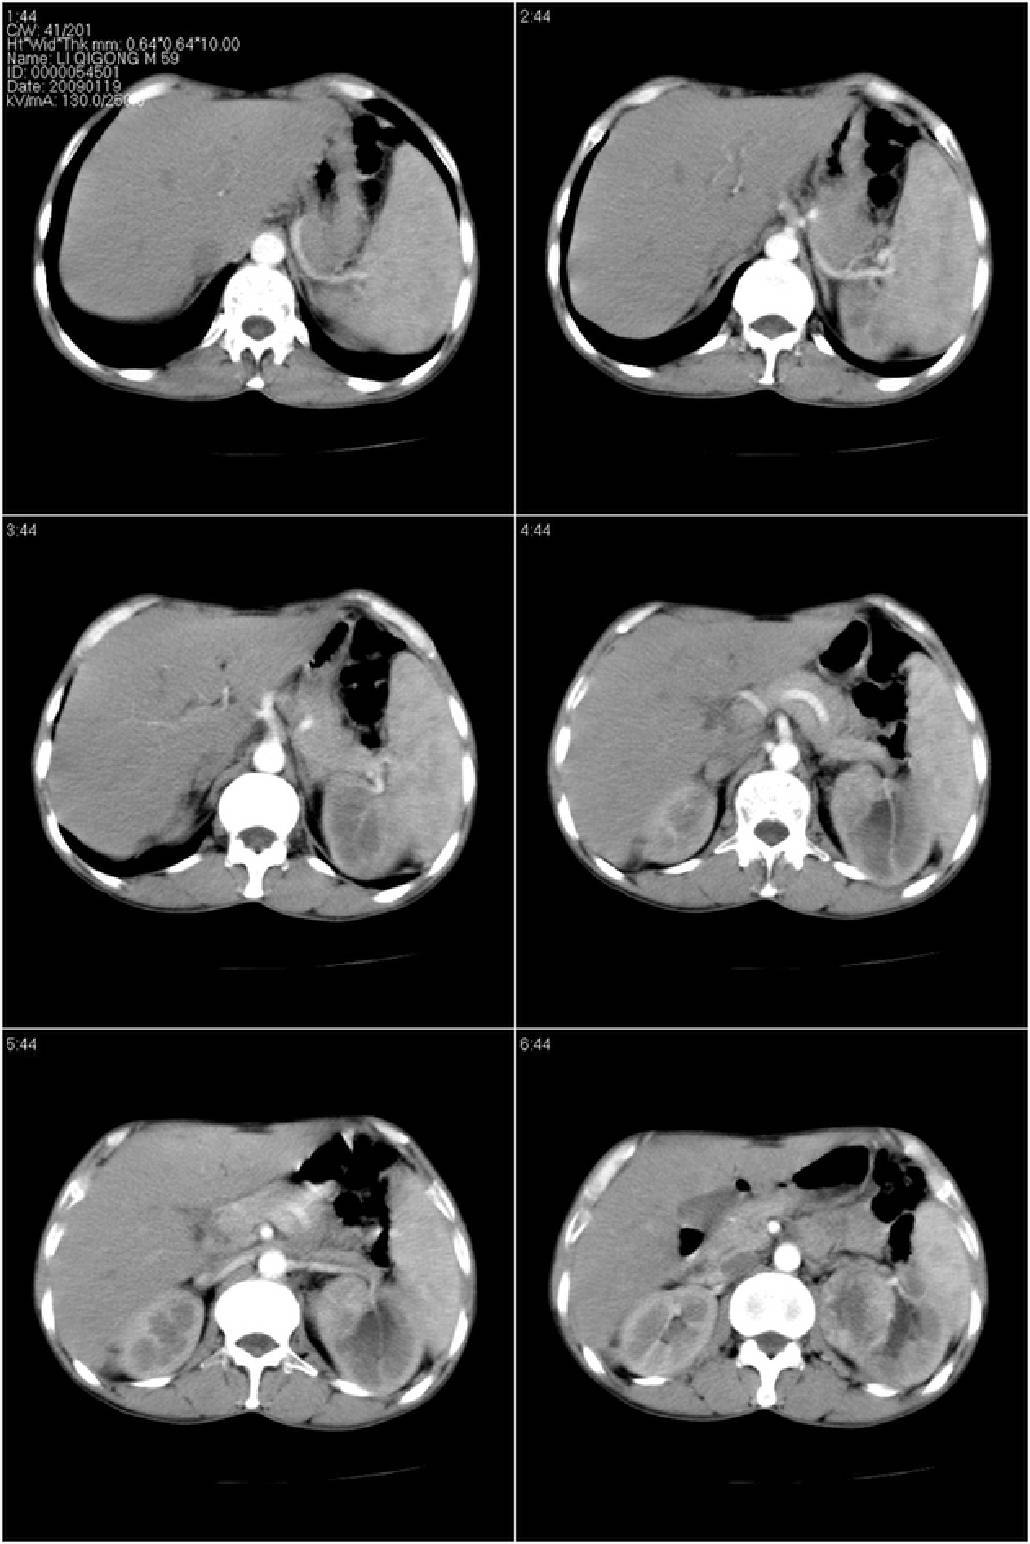

标题: CT17771:男性,59岁。体检发现左肾占位。

男性,59岁。体检发现左肾占位。自诉无尿血、尿痛。

无痛无血尿,左肾实质占位,有明显强化,中心坏死不规则,应该肾癌无疑。

应该考虑左肾癌并肾盂积水

诊断依据:

1、中老年男性.

2、左肾占位,呈不均匀性强化,中央有无强化的坏死区。

3、左肾门旁有侧枝开放,提示左肾静脉癌栓形成可能。

4、患者自诉无血尿,但不一定镜下无血尿。